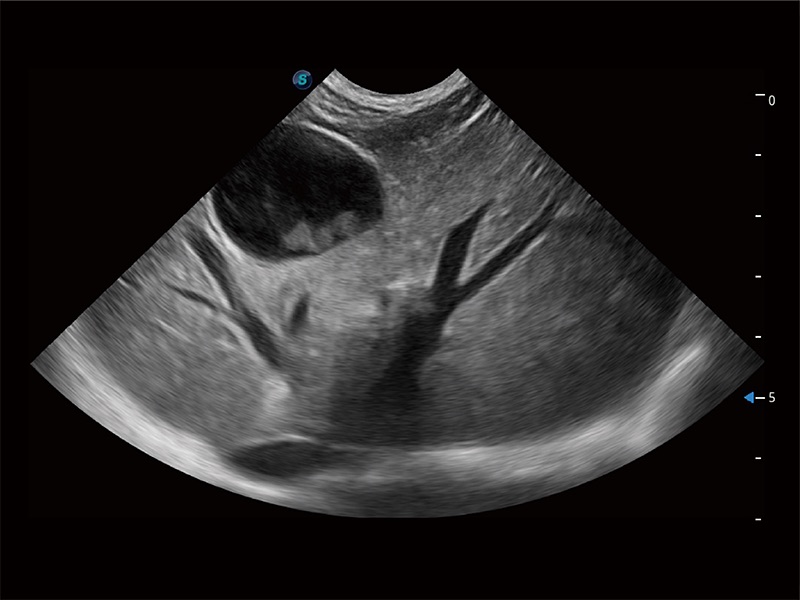

ProPet 80 配备了丰富的心脏探头群、先进的成像技术和专业的心脏测量工具,可帮助动物医生为不同体型和生理结构的动物提供心脏和心肌功能的全面评估。

实时用颜色表示心肌组织运动,观察和定量组织的运动情況,对快速检测与评估心肌的灌注和活性、电传导及心肌收缩和舒张功能等均能提供重要的诊断信息。